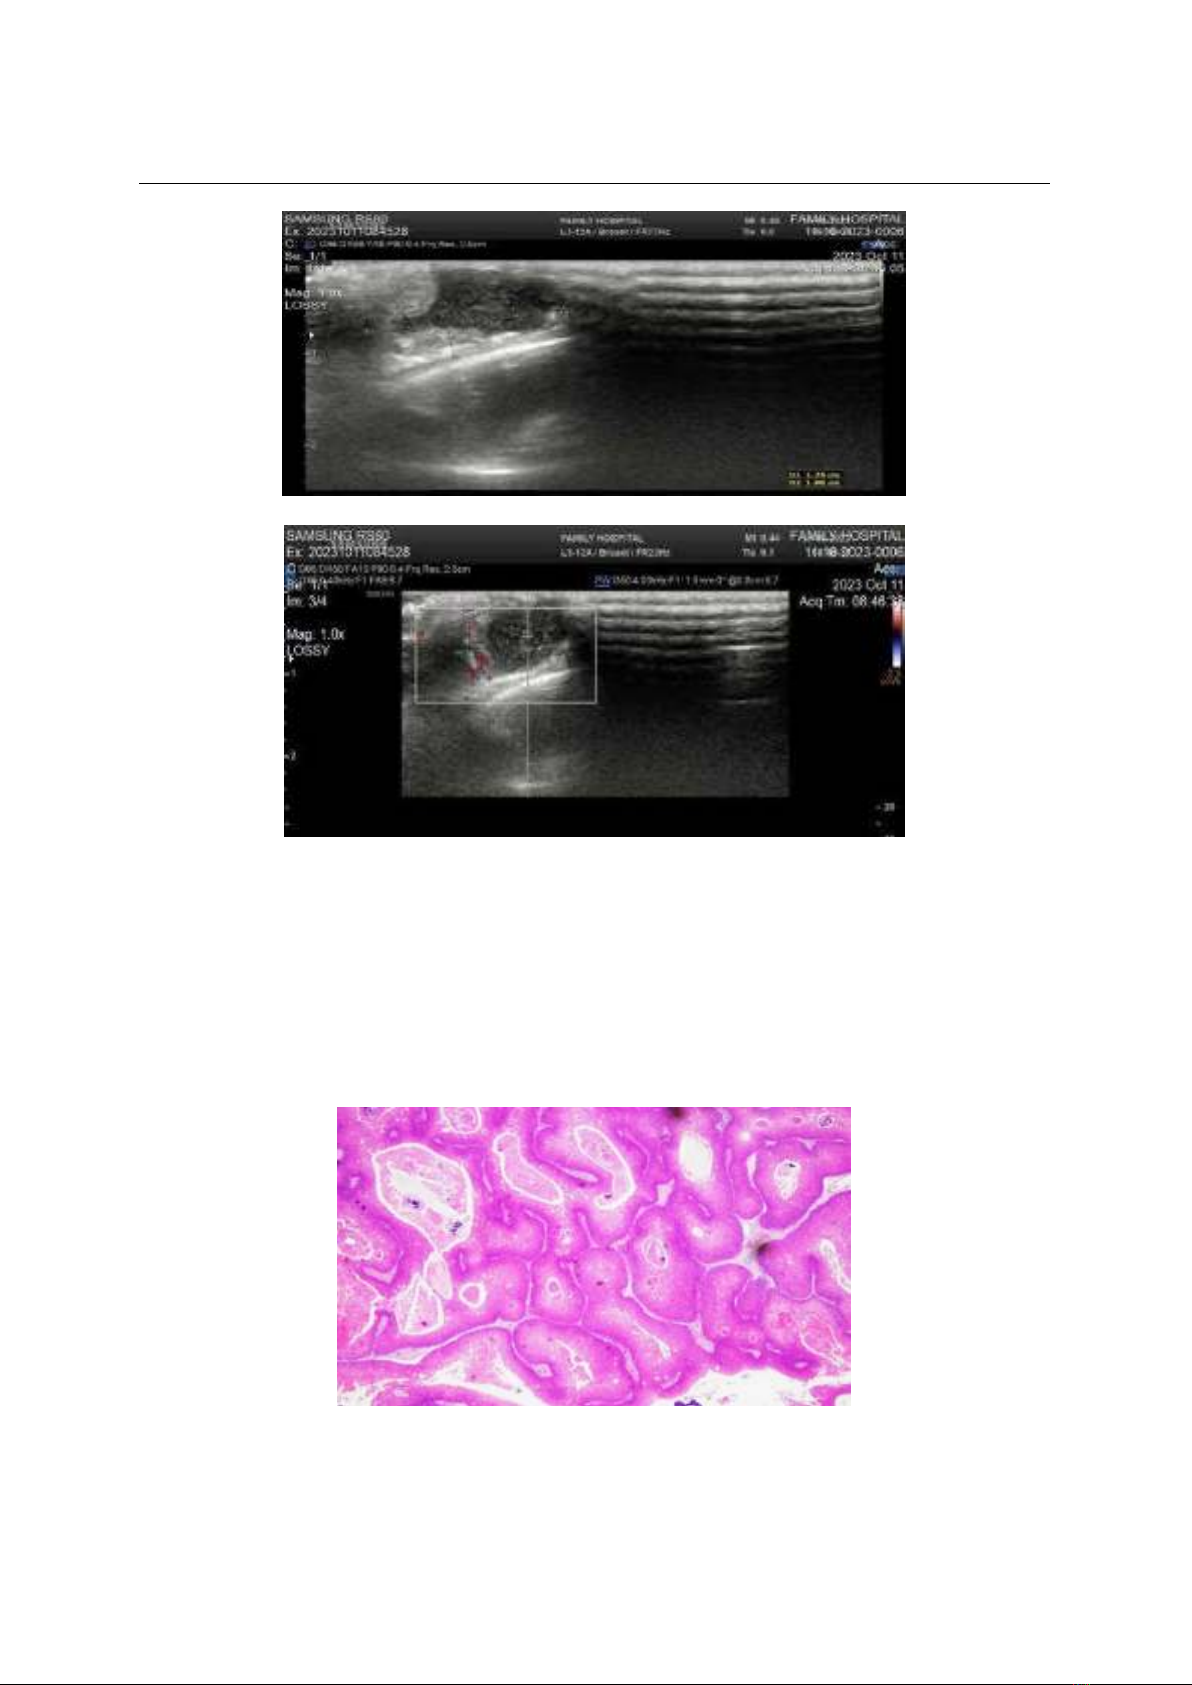

Bệnh nhân có khối u da đầu vùng thái

dương (P), xuất hiện hơn 10 năm, nay c vẻ

ln dần, không đau, đỏ, bề mt u trơn láng,

không có tóc mọc trên u, di đng tương đối,

kch thưc 1,5 x 1,7cm. Các xét nghiệm cơ bản

trong gii hạn bình thường, siêu âm cho thấy:

U mô mềm vng thái dương (P), cấu trúc hồi

m, không đồng nhất, kch thưc 10 x 17mm,

gồm phần đc, phần dch, c tăng m sau, c

tăng sinh mạch, phần dch không có tín hiệu

Doppler, bản ngoài xương thái dương không

thấy bất thường, chẩn đoán lm sàng u mỡ

vng thái dương P, (Hình 1&2).

Hình 1: Siêu âm khối u

Hình 2: Siêu âm Doppler khối u